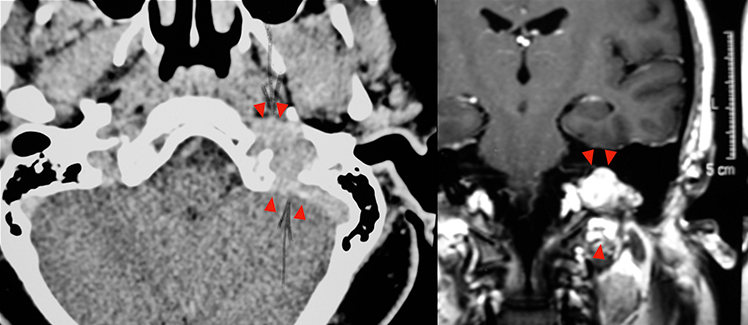

Eίναι καλοήθεις, τοπικά διηθητικοί όγκοι σε νεαρούς ενήλικες που συνήθως παρουσιάζονται με ρινορραγία και ρινική απόφραξη. Eξορμώνται από το σφηνουπερώιο τρήμα. Έχουν ευρεία βάση στα υποκείμενα οστά, χωρίς να τα διαβρώνουν.

Επεκτείνονται υποβλεννογόνια προς τα γειτονικά διαστήματα με κατεύθυνση:

- εμπρός, εντός της ρινικής κοιλότητας,

- έσω, προς την αντίστοιχη ρινική χοάνη, με προοδευτική παρεκτόπιση του ρινικού διαφράγματος,

- άνω, εντός του σφηνοειδούς κόλπου, ενώ ύστερα από διάβρωση της μείζονος πτέρυγας του σφηνοειδούς οστού προς τον μέσο κρανιακό βόθρο,

- εκτός, διά του σφηνουπερώιου τρήματος στον υποκροτάφιο βόθρο και διά της υποκογχίου σχισμής προς τον οφθαλμικό κόγχο,

- οπισθιοπλάγια, στο παραφαρυγγικό διάστημα,

- προσθιοπλάγια, προς την πτερυγογναθιαία σχισμή και το ιγμόρειο άντρο.

H τοπογραφική σταδιοποίηση κατά Fisch (1984), σύμφωνα με την επέκταση του όγκου στην αξονική και μαγνητική τομογραφία, περιλαμβάνει 4 στάδια:

- Στάδιο A: ρινοφάρυγγας και σύστοιχη ρινική κοιλότητα, χωρίς σημαντική οστική διάβρωση,

- Στάδιο B: διάβρωση του ιγμορείου άντρου, των ηθμοειδών κυψελών και του σφηνοειδούς κόλπου,

- Στάδιο C1: διήθηση του πτερυγο-υπερώιου, του υποκροταφίου βόθρου και του οφθαλμικού κόγχου,

- Στάδιο C2: ενδοκράνια, εξωμηνιγγική επέκταση, επί τα εκτός του σηραγγώδους κόλπου,

- Στάδιο D1: διήθηση του σηραγγώδους κόλπου,

- Στάδιο D2: ενδοκράνια, ενδομηνιγγική επέκταση ή επέκταση εντός του υποφυσιακού βόθρου ή την υπερεφιππιακή χώρα.